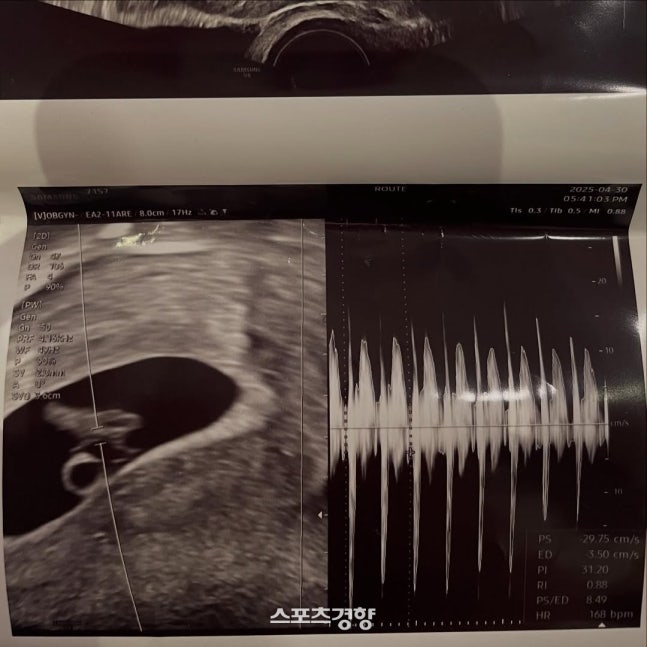

이와 함께 서민재는 자신의 연인과 함께 찍은 사진을 올리며 초음파 사진도 공개했다. 자신과 연인 사이에 아이가 생긴 것을 대중에게 알린 것이다. 이뿐 아니라 연인과 함께 찍은 다수의 사진을 함께 첨부했다.

서민재가 공개한 초음파 사진. 본인 인스타그램 계정